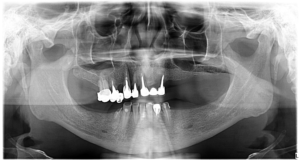

Pacientei i-a fost afectată fizionomia feței din cauza pierderii dinților.

În cazul pacientei noastre, pierderea dinților și a densității osoase a apărut din cauza bolii parodontale, ceea ce a dus la accentuarea ridurilor deja existente. Partea inferioară a feței s-a micșorat și a dus la un aspect îmbătrânit.

Pentru a-i reda funcționalitatea dentară, dar și o estetică armonioasă a fost nevoie de inserarea a 6 implanturi convențională la maxilar, și 6 la mandibulă.